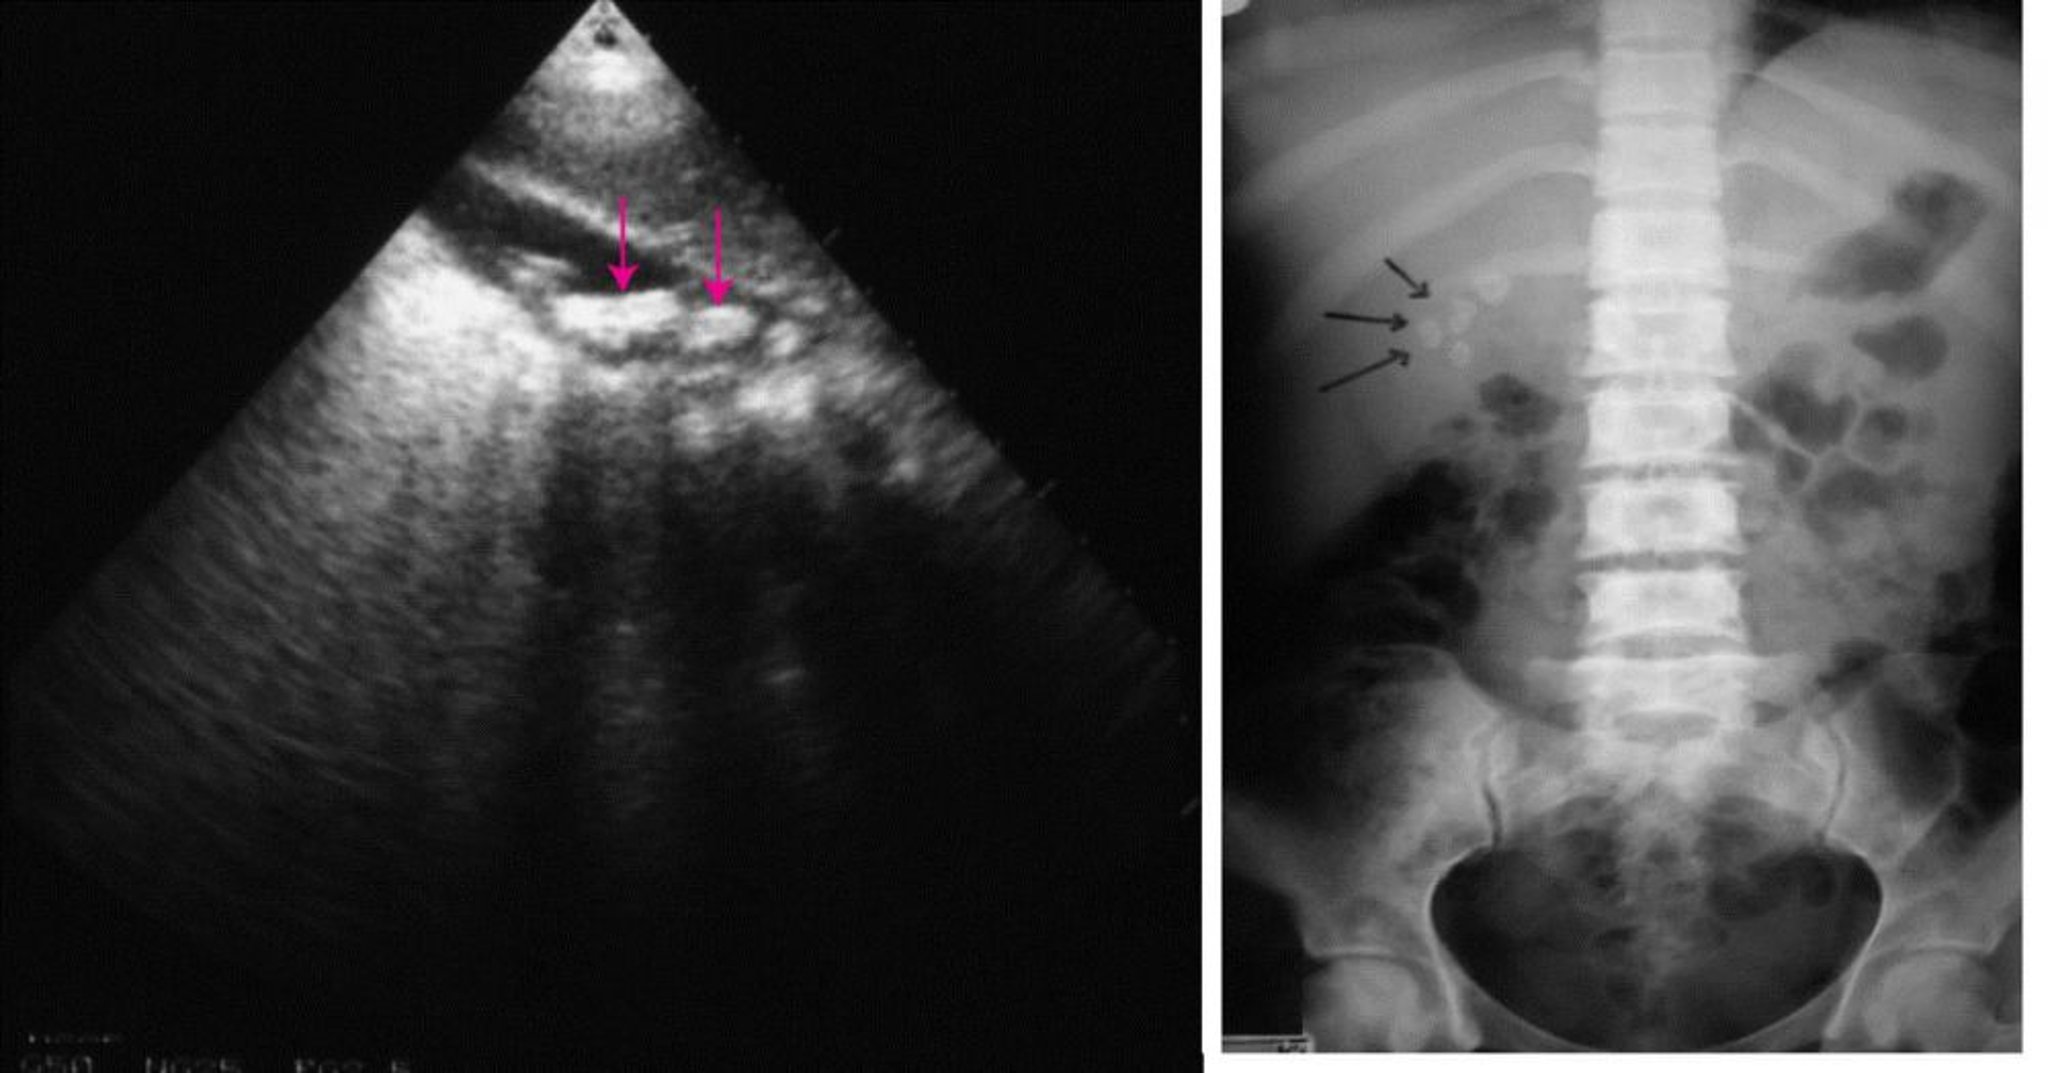

À esquerda, ultrassom abdominal mostrando vários cálculos biliares (setas). À direita, raio-x abdominal simples mostrando cálculos biliares radiopacos (setas).